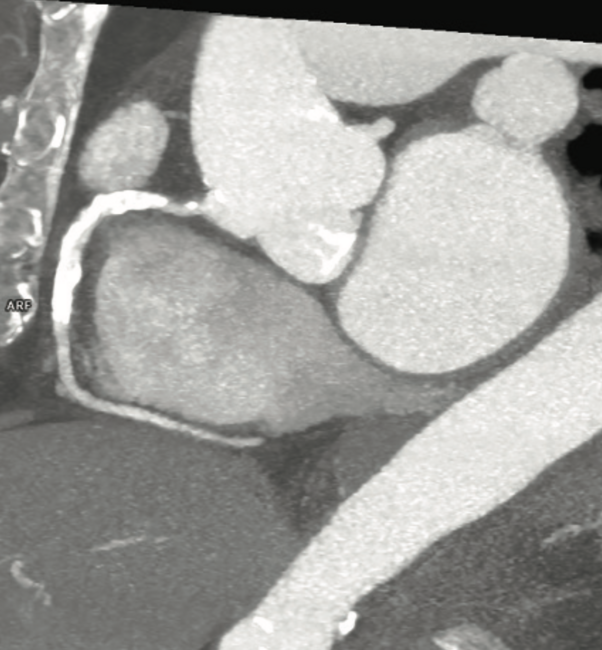

In this case, a 72-year-old female patient was referred for transcatheter aortic valve replacement (TAVR). Procedural assessment using fast temporal resolution computed tomography (66 ms, SOMATOM Force, Siemens Healthineers) revealed a high-grade stenosis in the mid right coronary artery (RCA) with severe calcifications. The patient underwent a successful percutaneous coronary intervention with initial rotablation. The ARTIS icono floor angiography system (Siemens Healthineers) OPTIQ imaging chain enabled consistent image quality regardless of angulation, with automated adaption of imaging parameters to maintain “as low as reasonably achievable” (ALARA) dose levels. The ClearStent feature showed full stent expansion with no indication of stent fracture. The final angiographic control demonstrated a good result without residual stenosis.*